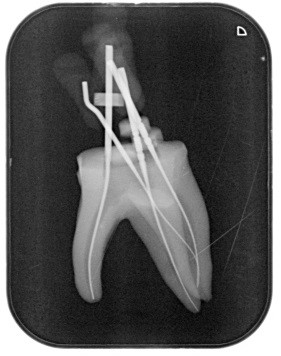

in vielen Fällen durch eine sogenannte Wurzelbehandlung erhalten. Wenn diese durchgeführt wird, wünschen wir uns natürlich gerade und weite Wurzelkanäle. Dies ist aber leider nur bei wenigen Behandlungen der Fall.

In den meisten Fällen besteht die Kunst also darin, einen Zahn trotzdem so lange wie möglich zu erhalten, selbst wenn das Wurzelkanalsystem sehr grazil und mit vielen Krümmungen versehen ist.

Dafür stehen in unserer Praxis unter anderem hochbiegsame Wurzelfeilen aus Nickel-Titan, ein elektronisches Längenmesssystem, ultraschallaktivierte Spülungen und ein Wurzelfüllungsmaterial zur Verfügung, das, wenn es erwärmt wird auch feine Verästelungen ausfüllen kann.